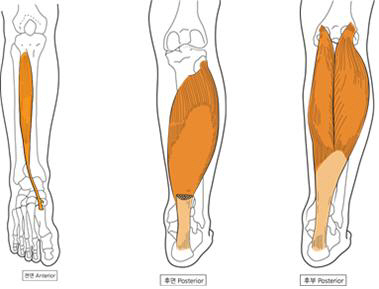

종아리는 우리 몸의 하체에서 가장 중요한 근육 중 하나인 **비복근(장딴지 근육)**과 가자미근으로 이루어져 있으며, 걷기, 달리기, 뛰기 등 다양한 움직임에 직접적으로 관여합니다. 따라서 종아리에 통증이 생긴다는 것은 다양한 원인과 관련이 있을 수 있으며, 이를 해결하기 위해서는 정확한 원인 파악과 적절한 대응이 필요합니다.

1-5. 근막 통증 증후군(MPS)

특정 근육에 트리거 포인트라는 압통 부위가 생겨 해당 부위뿐 아니라 인접 부위에까지 통증을 유발하는 증후군입니다. 종아리에 나타날 경우 종아리 근육 전체가 뻣뻣해지고 누르면 통증이 심해지는 특징이 있습니다.

2-5. 도수치료 및 물리치료

근막 통증 증후군이나 근육통이 만성화되었다면 전문가의 도수치료나 물리치료를 통해 트리거 포인트를 해소하고 근육의 이완을 유도할 수 있습니다.